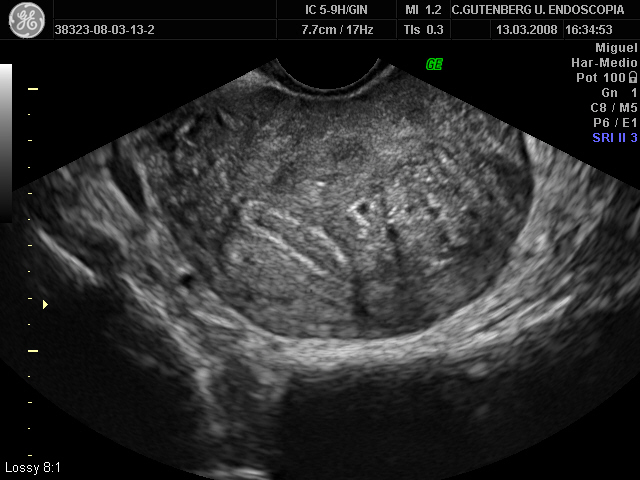

La ponencia sobre la repercusión de la adenomiosis en la fertilidad, comenzó con una respuesta clara y firme: la adenomiosis AFECTA a la fertilidad. Por un lado disminuye las tasas de implantación embionaria y por otro aumenta el doble la posibilidad de sufrir un aborto.

Además las mujeres con adenomiosis tienen más posibilidad de retraso de crecimiento intrauterino, de parto prematuro y de rotura prematura de membranas, por lo que podemos decir que la adenomiosis afecta también a la evolución del embarazo.

Es cierto que no todas las mujeres con adenomiosis padecen la sintomatología anteriormente citada. Un 30% de las pacientes con adenomiosis son asintomáticas. Los últimos estudios, revelan que a mayor extensión de la misma y mayor sintomatología (sobre todo menorragias o reglas muy abundantes), mayor afectación de la fertilidad.